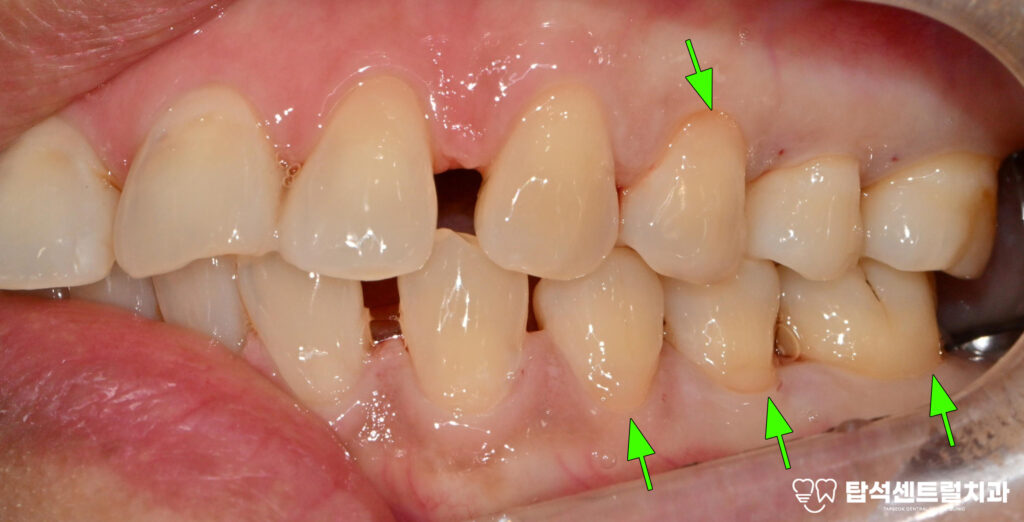

흔들리는 18번과 48번 사랑니 역시

발거가 필요한 상태였습니다.

사랑니는 안쪽에 위치해 있어

관리가 어렵고 염증을

유발하기 쉬운데요

이 기간 동안 10번과 40번대 사랑니 발치도

계획대로 진행되었고,

이후 충분한 시간이 흘러,

아래턱에 2차 수술 후

형태에 맞는 크라운을

올려두었습니다.

3개월 후 임플란트와 뼈가 잘 결합되면

크라운을 올려 치료를 종결합니다.

그동안 사랑니도 함께 뽑아낸

모습이 확인되고 있습니다.